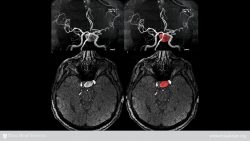

An aneurysm is a balloon-like bulge in the wall of a weakened blood vessel. If the bulging stretches the vessel wall too far, the vessel may burst. The aorta is the artery that carries blood from the heart to the rest of the body. An aneurysm in the aorta is called an aortic aneurysm. You can die if an aneurysm causes this main artery to burst and it is not treated in time. An aortic aneurysm may be located in your chest (thoracic aneurysm), but most are located below the kidneys in the lower stomach area (abdominal aneurysms).